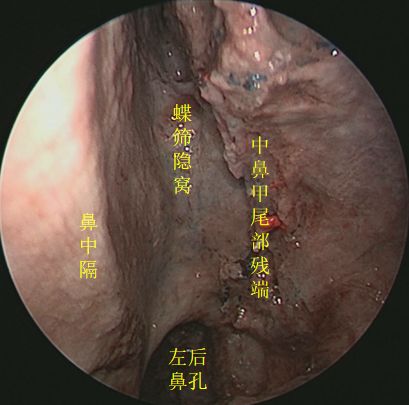

抵近观察左侧右鼻孔 ↓

↑ 去除左侧中鼻甲,抵近观察左侧蝶筛隐窝